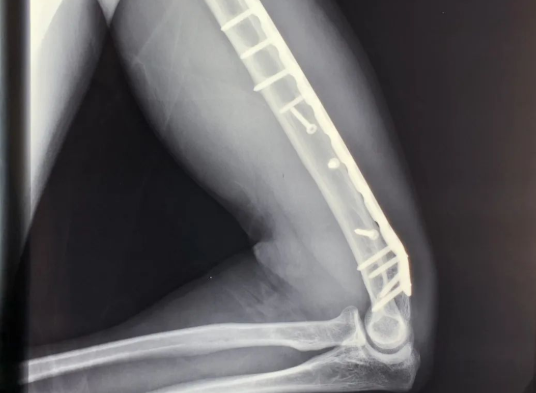

11根钢钉、20厘米钢板

永久保留在体内

拍完X光片

医生给出了伤情结论:

“右臂肱骨粉碎性骨折。”

20厘米长的钢板

11根钢钉

被植入固定在骨折处

由于固定伤处的钢板

距离桡神经过近

产生粘连

拆除钢板或会导致神经受损

进而影响右臂功能

医生建议将其永久保留体内